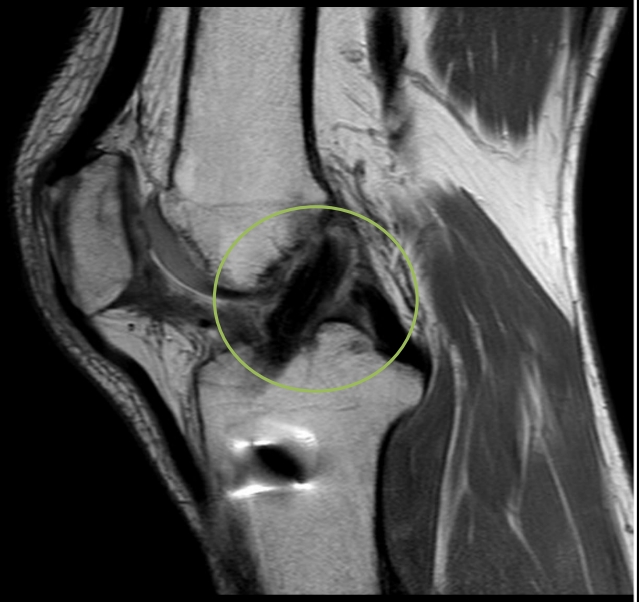

圖:36歲籃球好手李先生術後